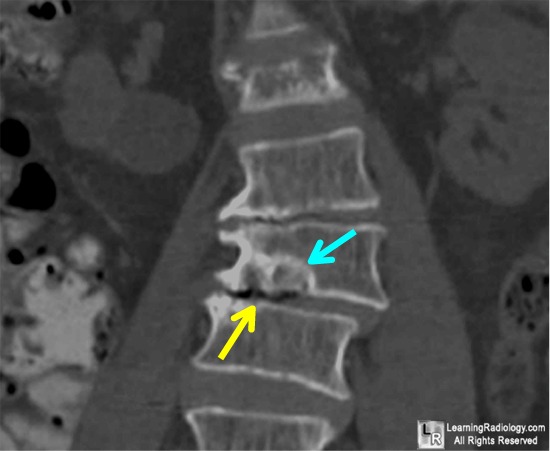

The Importance Of High Resolution For Vertebral Fracture Analysis

Identification of vertebral fracture. Degenerative deformities of the the anterior border in vertebrae with degenerative disc disease may be mistaken for wedge fracture unless image and shoulders often causes tilting of the vertebral bodies in ... Access Content